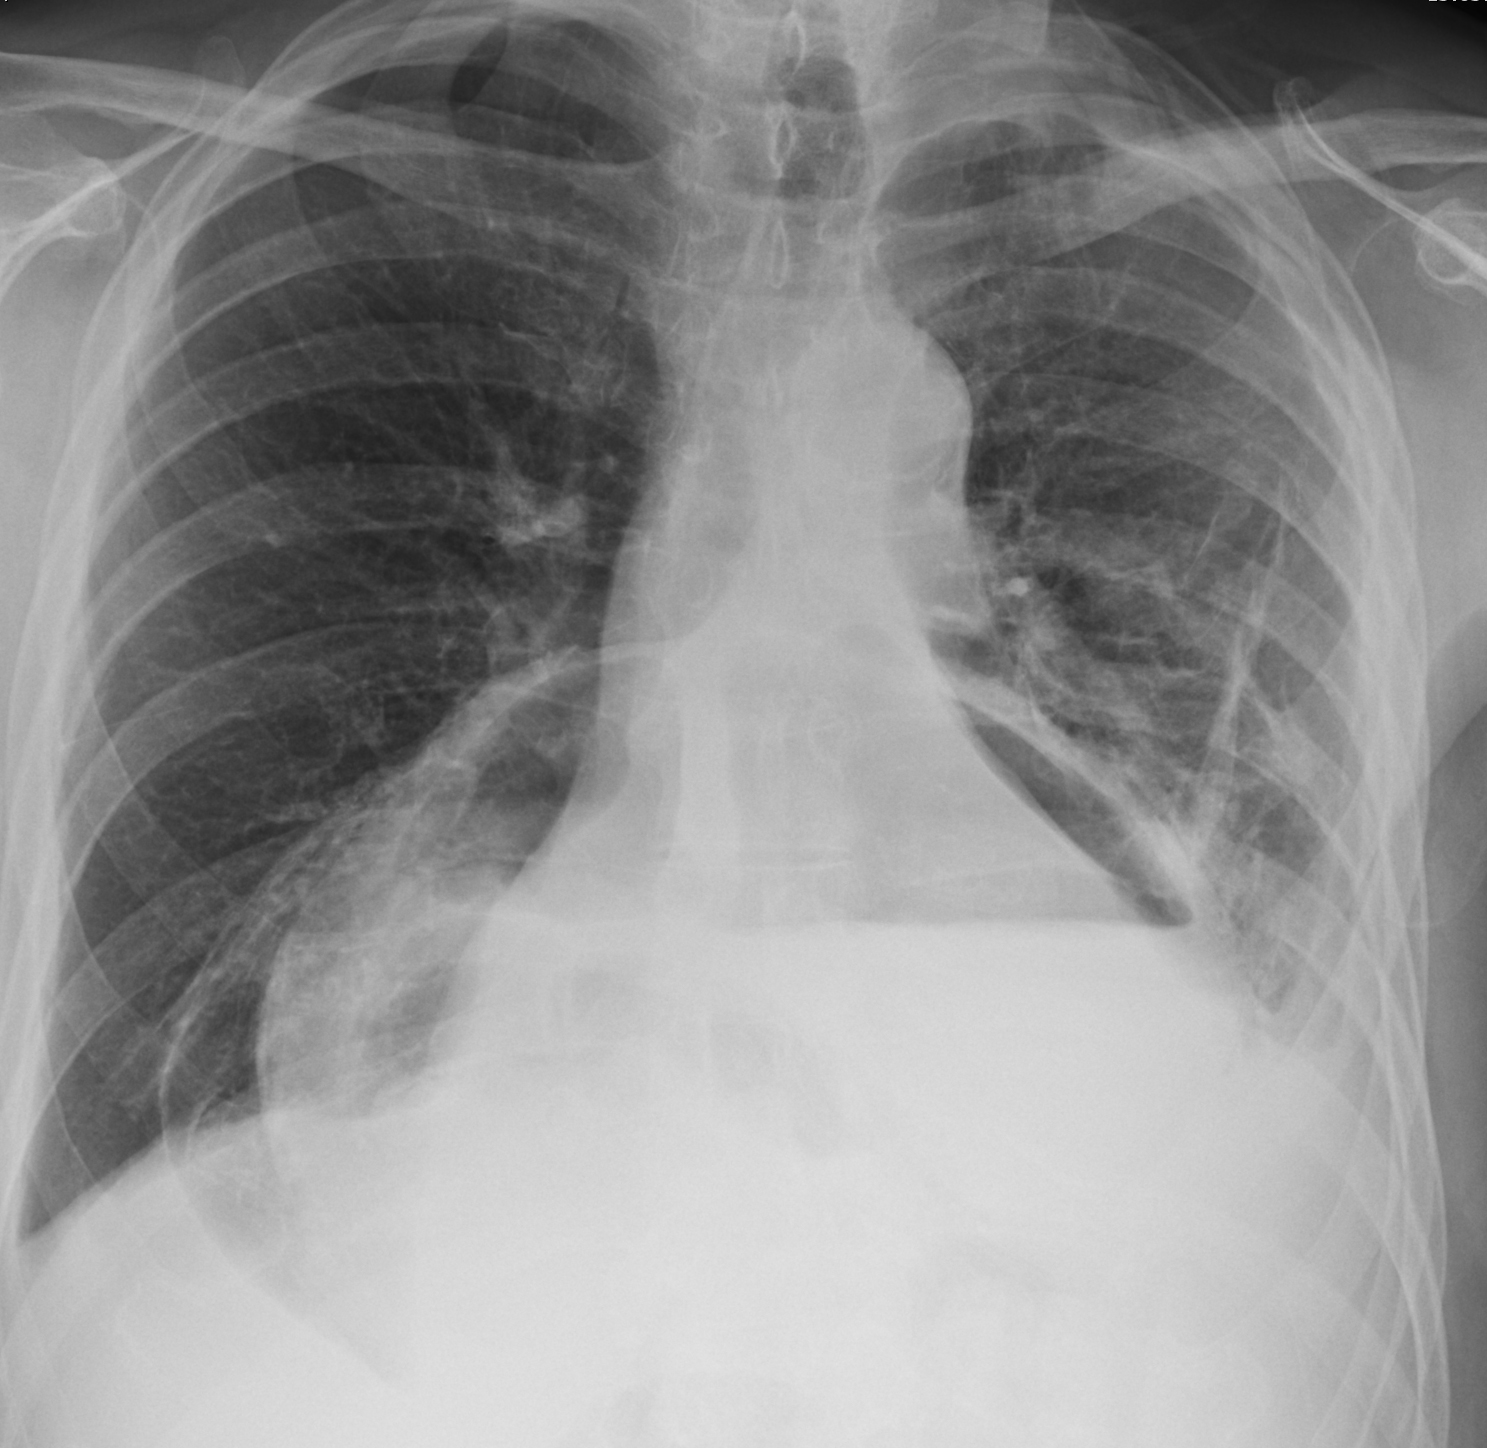

Hiatus hernia containing

stomach and transv colon